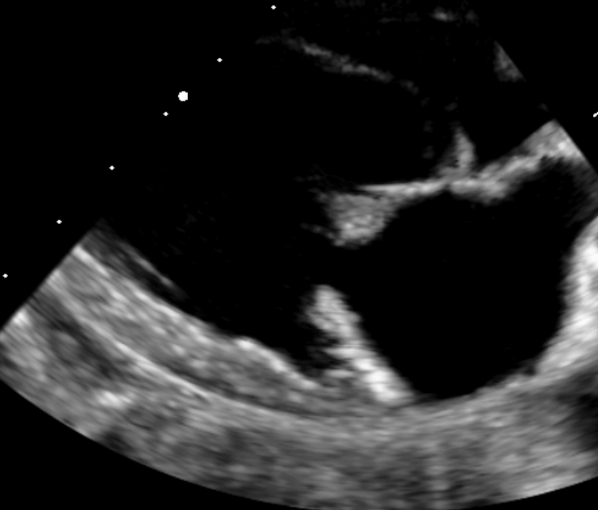

• Identifier, classifier et graduer les cardiopathies congénitales à partir des anomalies détectées en échocardiographie 2D, TM et Doppler.

• Interpréter de manière croisée les informations issues des différents modes échographiques (2D, TM, Doppler) pour affiner le diagnostic.

Analyse de cas cliniques illustrés par des images fixes et/ou des vidéos d’échocardiographie (2D, TM, Doppler).

Objectif : apprendre à repérer, décrire et interpréter les anomalies échographiques dans une démarche diagnostique rigoureuse, jusqu’à l’établissement de diagnostics différentiels.

Revue des bases en échocardiographie 2D, TM et Doppler appliquées aux cardiopathies congénitales.